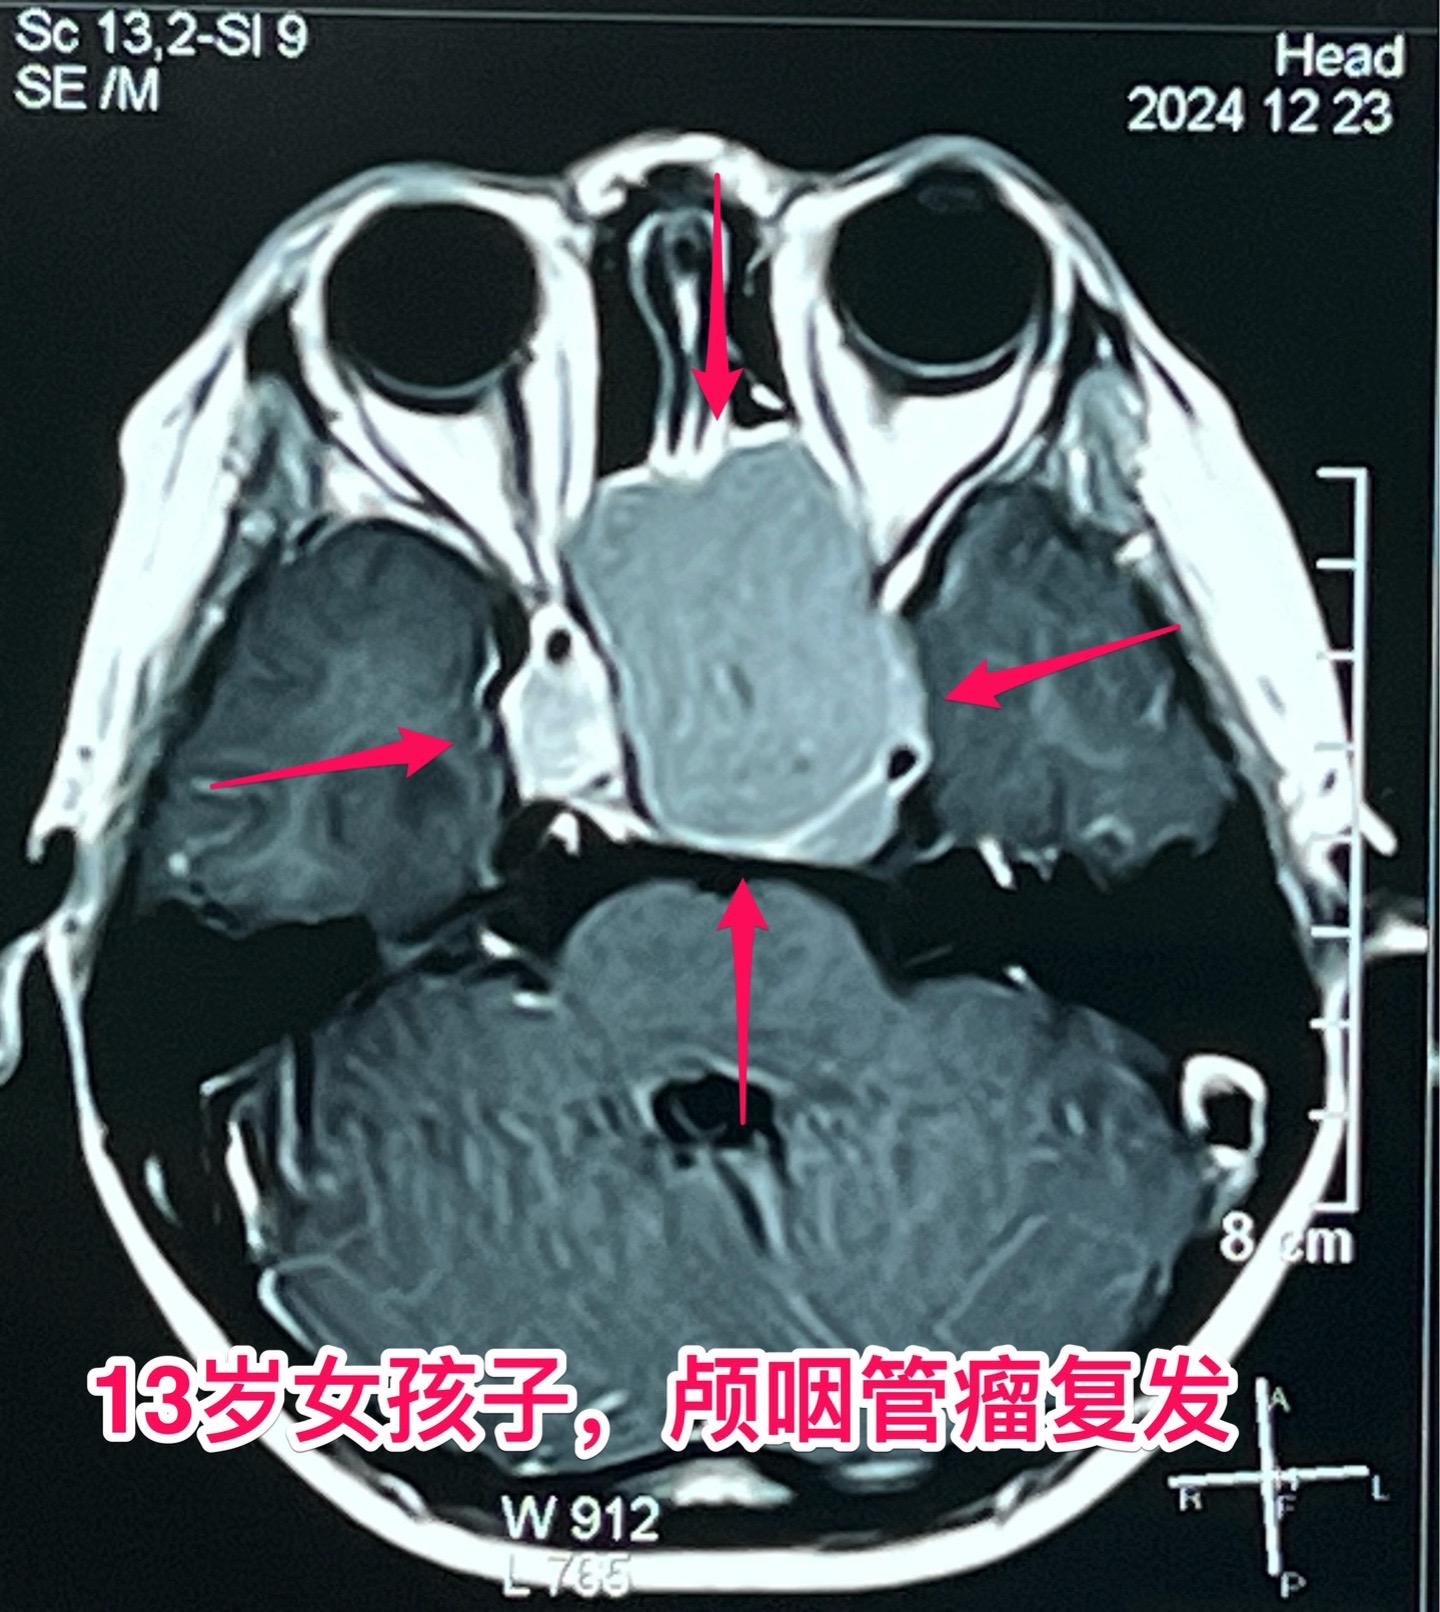

颅咽管瘤两次复发,右眼失明、左眼快失明了。13岁女孩子,因颅咽管瘤之前做过两次开颅手术。肿瘤又复发了,体积很大,垂体窝显著扩大,见图。 12月27日作了手术,将肿瘤完全切除。 这是第三次手术,手术前家长很担心左眼仅有的光感视力会不会变成全盲?会不会出现脑脊液鼻漏? 手术后患者很快就清醒了,左眼视力保住了,也没有脑脊液鼻漏出现。希望肿瘤不再复发。